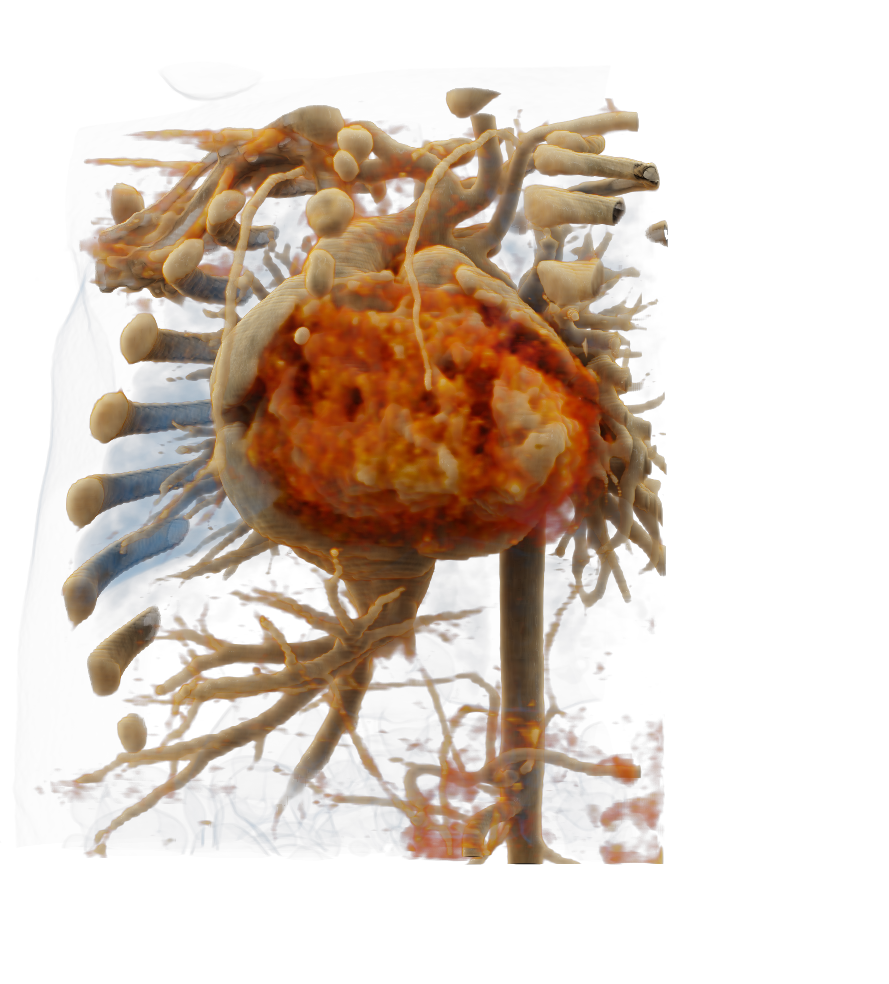

Visualize the smallest structures of the heart realistically without surgery? About the use of a prototype that makes this vision almost tangible.

Cardiac surgery is one of the most difficult procedures, and it gets even more complex when it comes to operating on tiny children’s hearts. Visualization techniques like cinematic rendering provide a detailed 3-D view of the patient’s heart and surrounding anatomy. But what happens when these images are turned into a hologram that can be rotated, zoomed, and looked at from all possible perspectives?